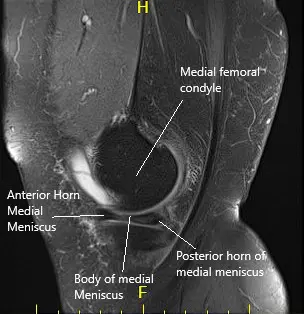

MRI of the left knee suggested a complex tear of the body and posterior horn the medial meniscus. Moderate patellofemoral chondromalacia associated moderate-sized joint effusion and capsular inflammation.

MRI of the left knee in sagittal and coronal sections.